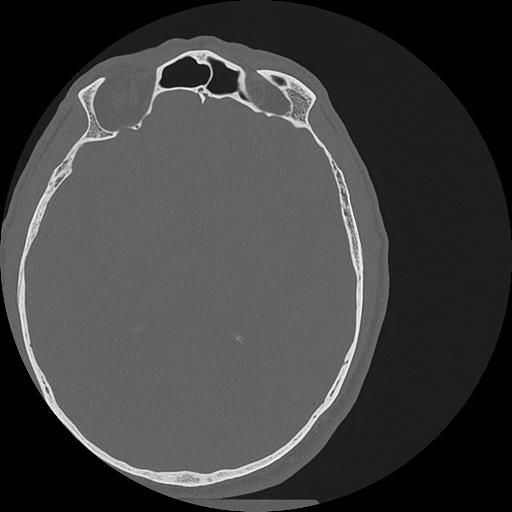

7 HUESO,,Vol,0.5,HUESO,,